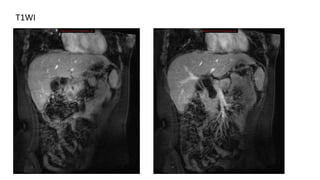

MRI

• T1WI : hypointense dilatation of bile duct

• T2WI : hyperintense

T1WI

T2WI

Type III choledochal cyst in coronal T2WI

MRI • T1WI :hypointense dilatation of bile duct • T2WI : hyperintense

Type III choledochalcyst in coronal T2WI